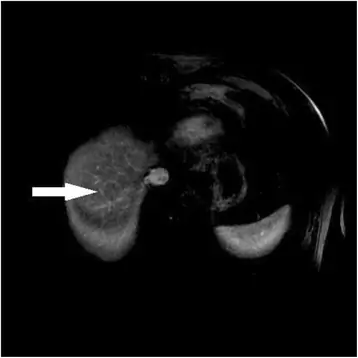

Внутриклеточный липид, обнаруженный в узле при двойном эхо в и противофазной МРТ, взвешенной по фазе T1, является дополнительным открытием, которое, как было показано, является достаточно специфичным для ГЦК. Это может быть полезным дополнением к набору инструментов при рассмотрении поражения с неспецифическими характеристиками усиления, поскольку внутриклеточный липид очень редко встречается в регенеративных или диспластических узлах (51) (рис. 3).

Рисунок 3

71-летний мужчина с циррозом гепатита С. Сигнал выпадает на противоположной фазе изображения (б) по сравнению с в фазе изображения (а). Результаты представляют внутриклеточный липид в опухоли ГЦК

Изображение в полном размере